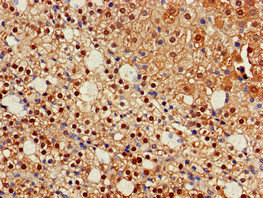

Immunohistochemistry of paraffin-embedded human adrenal gland tissue using CSB-PA010989EA01HU at dilution of 1:100